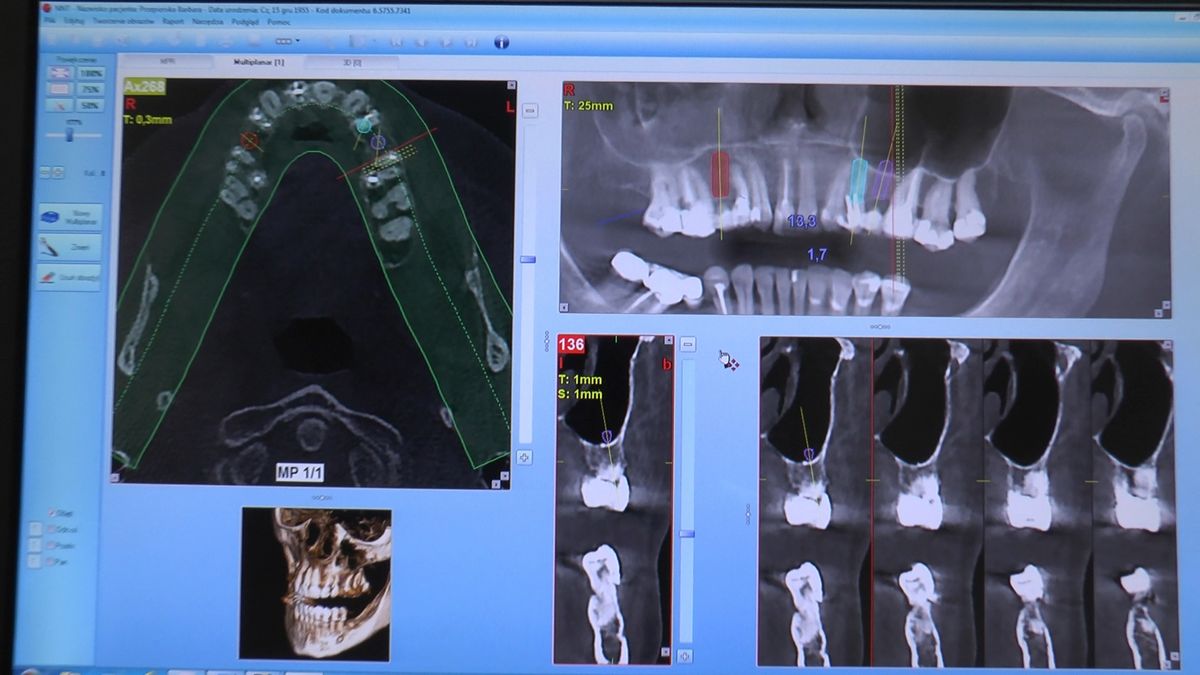

W ostatni weekend czerwca 2018 roku kursanci II Sezonu Preludium Implantologii odbyli piątą, finałową sesję, która w całości podporządkowana była praktyce. W ciągu dwóch dni zabiegowych Lekarze uczestniczący w szkoleniu przeprowadzili szereg zabiegów pod kierunkiem dr n.med. Violetty Szycik. Wszczepili 17 implantów oraz przeprowadzili ekstrakcje i zabiegi regeneracyjne kości. Zabiegi były wykonywane także w sedacji dożylnej z udziałem specjalisty anestezjologii i intensywnej terapii dr Jolanty Grzybowskiej. Preludium implantologii to nowy program edukacyjny dla adeptów implantologii stomatologicznej, którego celem jest wprowadzenie do implantologii poprzez pozyskanie wiedzy w szerokim zakresie i uwzględnieniem szczegółów mających decydujące znaczenie dla powodzenia leczenia implantologicznego. Ale tak jak wszystkie szkolenia w Instytucie Vivadental, w tym wiodące Practiculum Implantologii, zorientowane jest na praktyce i samodzielnym wykonywaniu zabiegów pod kierunkiem Mentora. To najlepsza edukacja w medycynie zabiegowej, a zarazem najlepszy start do implantologii.